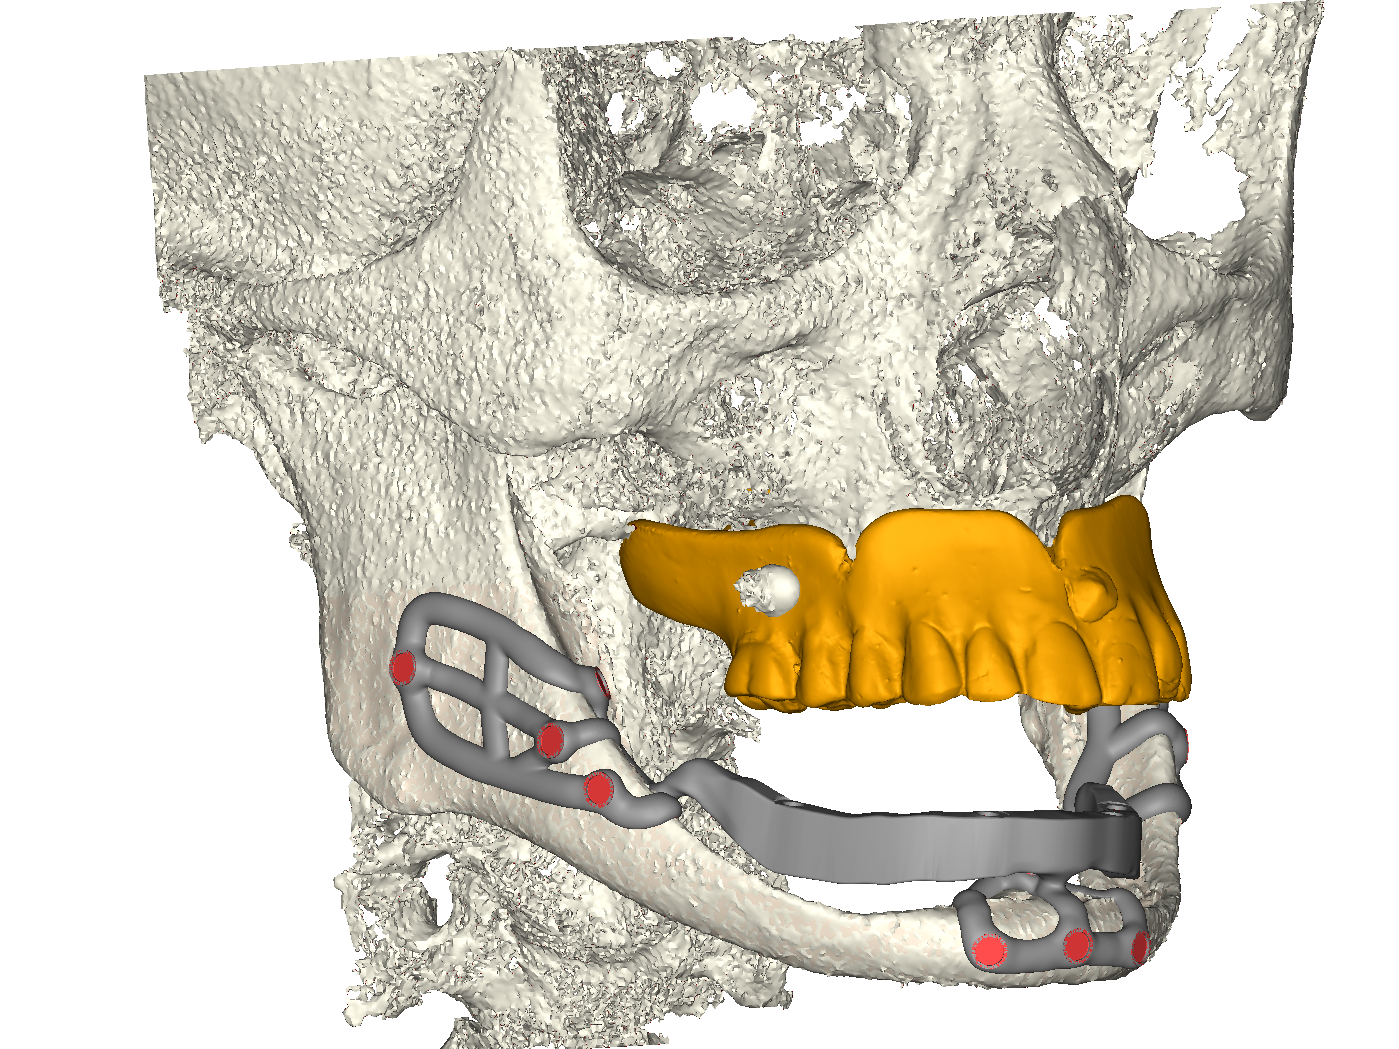

Il dispositivo prevede dunque tre punti di appoggio osseo stabilizzato a mezzo viti di sintesi (diametro 2 mm, lunghezza 6mm autofilettanti) e contestualmente tre emergenze, congiunte ad una barra extramucosa che funge da struttura di sostegno della contro-barra fresata rimovibile (fig. 3a, b, c), a sua volta ancorata ad attacchi a sfera. Contestualmente alla progettazione dell’impianto iuxta osseo, l’Odt. Fabio Marchiori, ha provveduto alla progettazione della parte protesica del dispositivo. Si è trattato, nello specifico, come appena descritto, di una controbarra ibrida: l’anima della struttura è stata progettata e stampata in titanio medicale (mediante tecnica SLM con Ti grado 23) e la componente anatomica è stata fresata da un disco di composito. La controbarra viene ancorata alla barra portante dello iuxta osseo per mezzo dei già citati attacchi a sfera, che sono stati avvitati per mezzo di filettatura dell’impianto stesso.

Progetto iuxta tripodale

Fig. 3(a). Progetto iuxta tripodale.

Vista frontale iuxta in posizione

Fig. 3(b). Vista frontale iuxta in posizione.